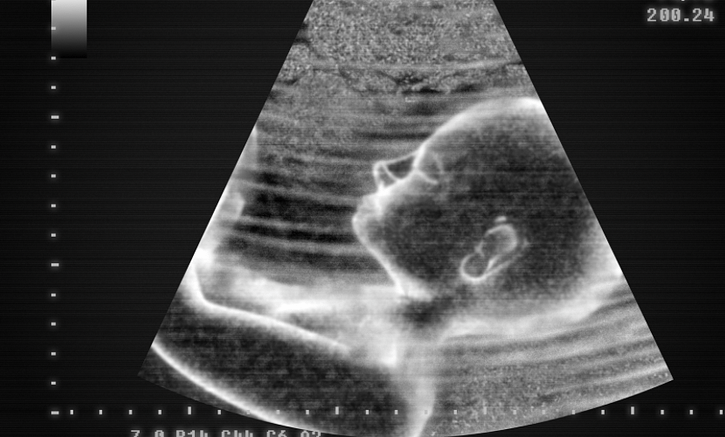

Anne karnında bebek, sanıldığı gibi tamamen sessiz bir ortamda değildir. Aksine, anne rahmi oldukça sesli bir yerdir ve bu sesler bebeğin gelişimi için önem taşır. Anne adayları genellikle bebeklerinin hangi sesleri duyduğunu ve bunların bebeğin üzerinde nasıl etkiler bıraktığını merak ederler. İşte bu konuda bilmeniz gerekenler!

Bebekler, hamileliğin yaklaşık 16. haftasından itibaren seslere duyarlı hale gelmeye başlar. Ancak bu süreçte işitme yetisi henüz tam gelişmemiştir. 24. haftadan itibaren bebekler daha net bir şekilde sesleri duymaya ve tepki vermeye başlar. Örneğin, yüksek bir ses duyduklarında irkilebilir ya da annenin sakinleştirici bir konuşması sırasında hareketleri yavaşlayabilir.